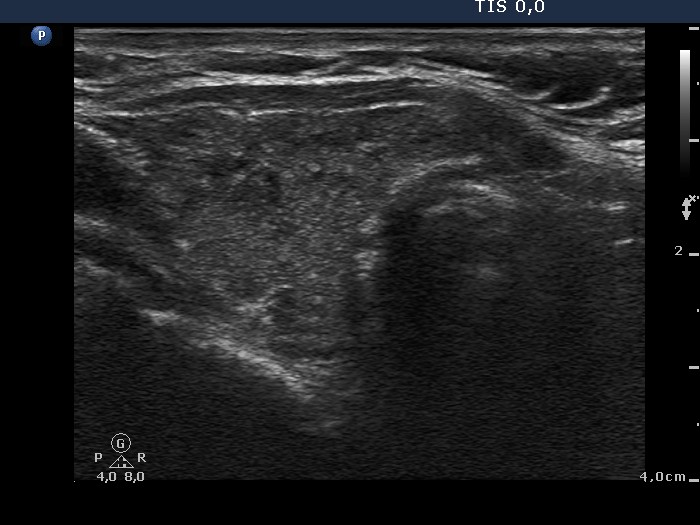

Chronic lymphocytic thyroiditis - Case 31.

Initial investigation in hypothyroid state (ultrasonographic picture 2)

Right lobe, longitudinal scan. There are several small discrete hypoechogenic areas. These do not fit nodule.